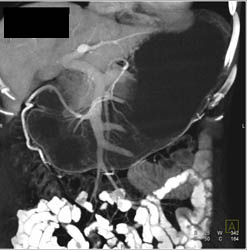

Diagnosis

Gastritis